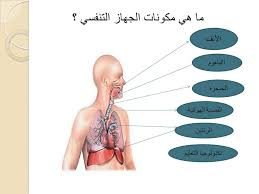

جهاز التنفس

احد اجهزة الجسم له وظيفة حيوية ومهمة مكون من عدة اعضاء تعمل معا من ان تؤدي وظيفة جهاز التنفس وهي ادخال الاوكسجين الموجود في الهواء الى الدم بواسطة الشهيق واخراج ثاني اوكسيد الكربون من الم الى الخارج الجسم بواسطة الزفير

اعضاء جهاز التنفس

الانف

البلعوم

الحنجرة

القصبة الهوائية

الرئتين

الحجاب الحاجز

الاضلاع